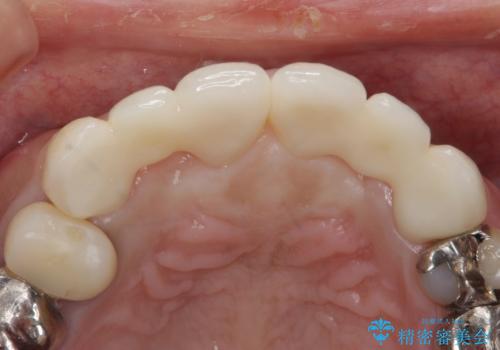

綺麗な被せ物が入りました。

最終的な被せ物は抜歯を行なってから半年経ってから形を整えて型取りを行います。